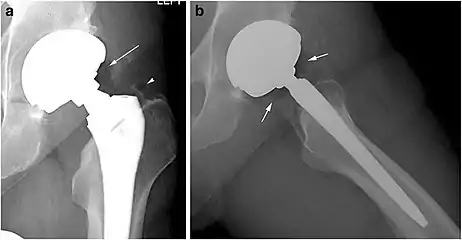

Pneumarthrosis is the presence of air in a joint. Its presentation on radiography is a radiolucent cleft often called a vacuum phenomenon, or vacuum sign.[7] Pneumarthrosis is associated with osteoarthritis and spondylosis.[8]

Pneumarthrosis is a common normal finding in shoulders[7] as well as in sternoclavicular joints.[9] It is believed to be a cause of the sounds of joint cracking.[8] It is also a common normal post-operative finding at least after spinal surgery.[10] Pneumarthrosis is extremely rare in conjunction with fluid or pus in a joint, and its presence can therefore practically exclude infection.[8]